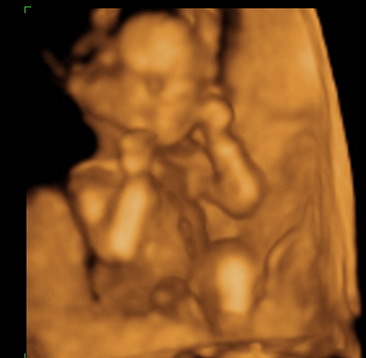

Gratula a kukishoz! Úgy tűnik minden Kisfiúnak ez a szokása! Apa akkor nagyon büszke :lol: :lol: ! Rajta múlt :D ! Kép KUKAC

Kép levitáció Kép Orr+fülfogás

Kép BOX

Kép Lúdtalp nincs :):)lábfej torna Kép Kép Álmos vagyok

Kép guggolás Kép Tipikus pasi-láb között matatás

Kép Nyújtózás

Kép Hello Kép Elég volt, most már alszom